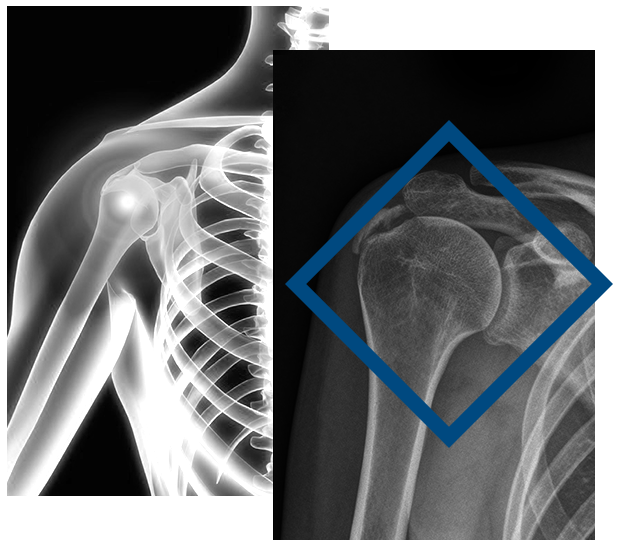

Η πολύ καλή κλινική εξέταση θα καθορίσει την αιτία του πόνου. Για να γίνει σωστή διάγνωση απαιτείται ακτινολογικός έλεγχος ώστε να εκτιμηθεί η ανατομία των οστών στην περιοχή του ώμου και να διαπιστωθεί τυχόν εναπόθεση αλάτων ασβεστίου στους τένοντες που μπορεί να προκαλέσει τενοντίτιδα. Με τη μαγνητική τομογραφία θα διαπιστωθεί ο βαθμός της τενοντίτιδας και ενδεχόμενη ρήξη των τενόντων η οποία επηρεάζει και τη βαρύτητα της πάθησης.